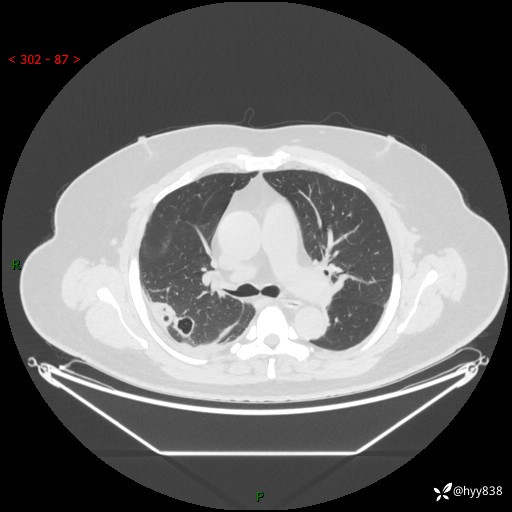

病例信息

性别:男

年龄:48岁

简要病史:发热来诊(门诊病人)

胸部CT平扫